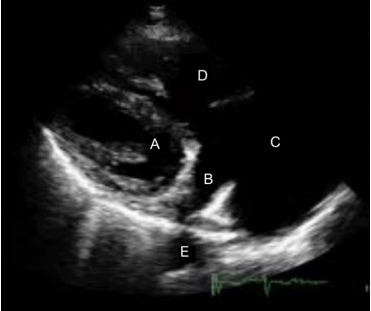

Na figura a seguir, identifique a estrutura representada em B.